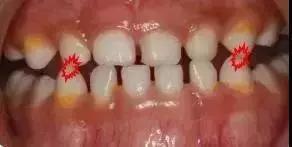

01、调磨法

这里必须强调一哈,调磨法一定要医生进行操作,千万莫私自行动。一般情况下,两周调磨一次,1-3个月就可以纠正“地包天”了。